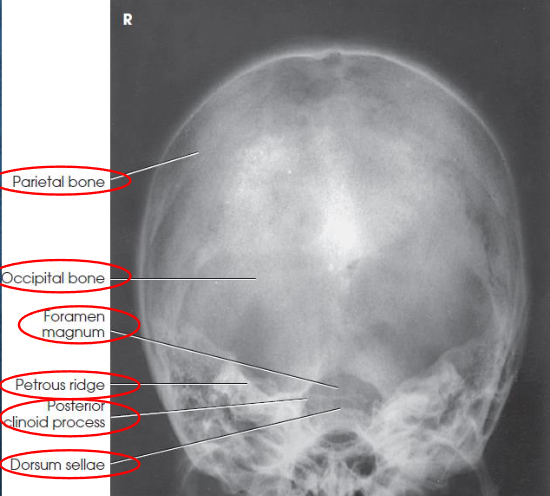

AP axial (Towne) skull image criteria

no rotation:

equal distance from lateral border of skull to lateral margin of foramen magnum

symmetric petrous ridges

dorsum sellae and posterior clinoid process visible within foramen magnum

penetration of occipital bone without excessive density at parietals